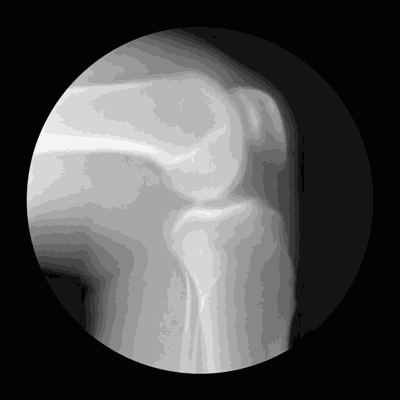

关节僵硬

它们最怕5个字

关节是骨骼之间的连接点,一旦关节出了问题,人的行动力就会受限,久之人就垮了。

关节不好的患者,对心血管系统、呼吸系统、骨骼肌系统等会造成一定影响。因关节病长期卧床的老年人,也会引发骨质疏松、褥疮、消化系统疾病。

关节在生活中最怕几个字:

怕老

随着年龄的增长,人体软骨营养缺乏,骨骼中的无机物增多,骨骼弹力与韧性减低,易导致关节软骨和骨退行性病变。

怕胖

体重增加,下肢关节承重的压力也会增加,引起体位、步态变化,改变关节的生物力学,发生膝内翻或膝外翻,也就是常说的“O”形腿或“X”形腿。

怕伤

在运动、出行的过程中,如果出现急性外伤,一定要及时去医院治疗,以免留下后遗症。

不及时治疗或充分休息,容易留下病根,比如“习惯性崴脚”。

怕勤

关节用得太狠,容易导致机械磨损,破坏软骨。

频繁爬山、爬楼等是非常伤害关节的。建议大家平时通过慢跑、游泳锻炼,既不损伤关节又能锻炼。

怕冷

关节受凉会引起疼痛,易导致关节僵硬。